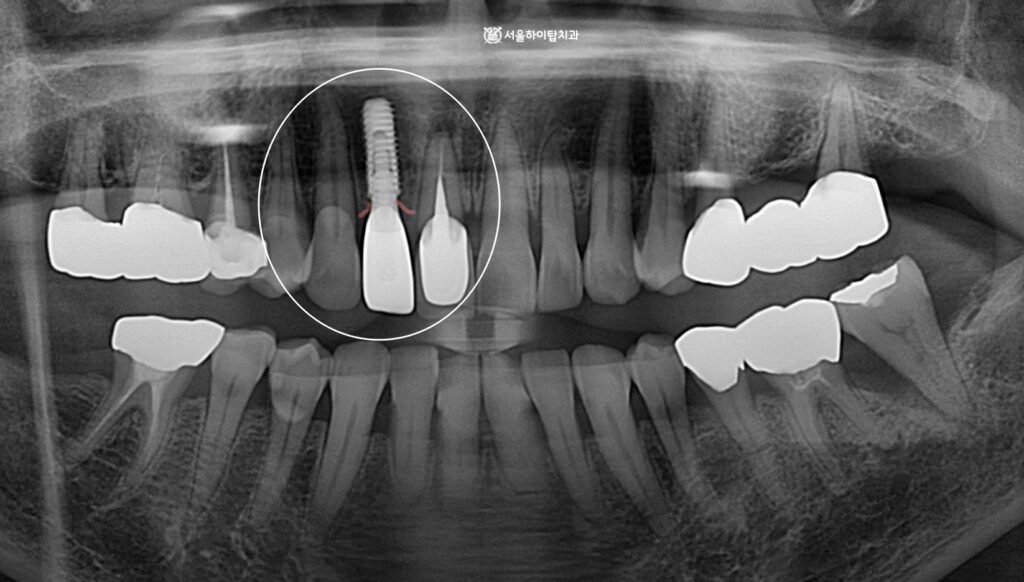

초진 파노라마 엑스레이입니다.

십정동 치과 에서 표시해 둔 부위를 보면

상실된 앞니를 확인할 수 있습니다.

치아가 상실되면 인접치와 치조골에서는 위치 변동과 골 흡수가 나타날 수 있는데,

다행히 해당 X-ray에서는 눈에 띄는 변화는 없는 것으로 보입니다.

다만, 주변 골질이 다소 좋지 못한 모습은 확인되며,

이는 뼈의 밝기와 내부 패턴을 통해 간접적으로 판단할 수 있습니다.

정상 치조골은 비교적 선명하고 균일한 밝기를 보이지만,

골밀도가 낮아지면 해면골 패턴이 성글게 보이거나

피질골의 윤곽이 흐릿하게 나타나는 특징을 보입니다.

쉽게 말씀드리면, 단단한 뼈처럼 하얗게 보이지 않고

상대적으로 검게 비어 보이는 경향이 있다고 이해하시면 됩니다.